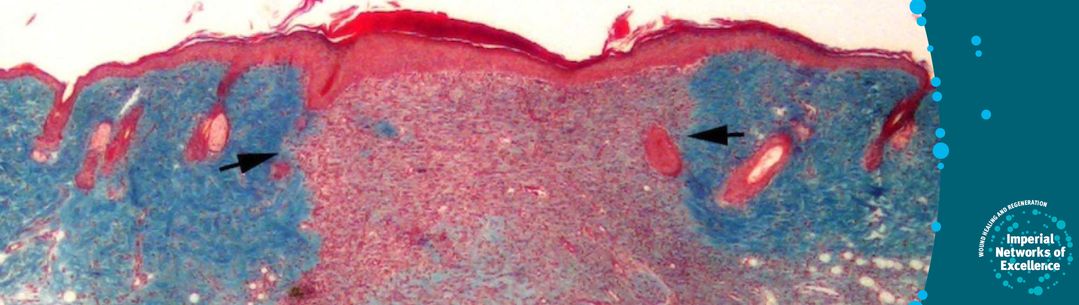

Microscope image of a blue and red cross section of cells